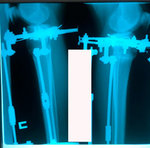

Дата операции - 24.10.2019г.

Дата снятия аппаратов - 22.01.2020

Срок сращения - 89 дней.